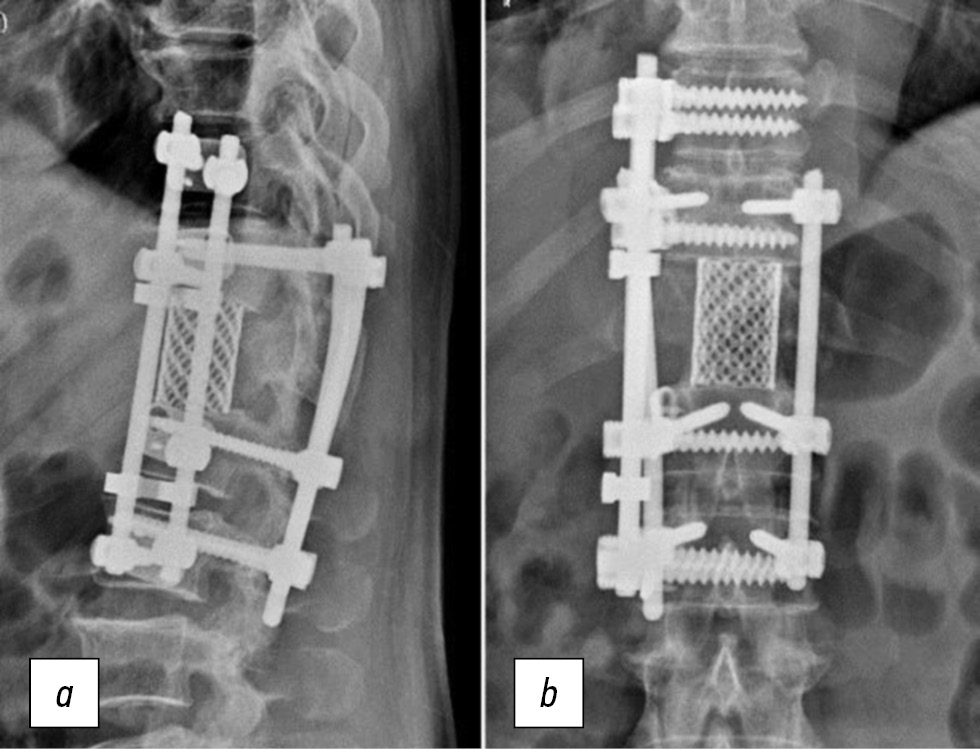

Проведены лучевые обследования (рентгенография, компьютерно-томографическое (КТ) исследование), при которых выявлен сегментарный кифоз с вершиной на уровне Th12 позвонка. Угол кифоза составил 28°. Грудопоясничный отдел позвоночника фиксирован транспедикулярной системой, инструментированы позвонки Th11, L1 и L2. Целостность элементов конструкции не нарушена (рис. 1).

Рис. 1. Рентгенограммы позвоночника больного Е., 71 год, прямая (a) и боковая (b) проекции.